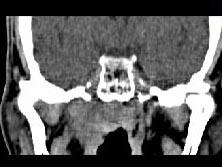

男,52岁,血涕二月余,CT如图所示,最可能的诊断为()A.鼻咽癌B.咽旁混合瘤C.咽部神经纤维瘤D.小涎液腺瘤E.咽旁脓肿

问题 男,52岁,血涕二月余,CT如图所示,最可能的诊断为()

选项 A.鼻咽癌 B.咽旁混合瘤 C.咽部神经纤维瘤 D.小涎液腺瘤 E.咽旁脓肿

答案 A